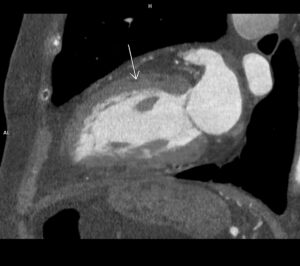

Figurile 2 si 3 reconstrucţii volumice aortă toracică

Video 3: sagital MIP angio torace

Discuţie caz nr 86: Valva aortică este morfologic bicuspidă la 1% din populație și asociază, cu timpul, creștere de calibru a aortei ascendente datorită fluxului turbulent determinat de modificarea de morfologie a valvei aortice – în unele cazuri această malformație congenitală asociază modificare de calibru a aortei descendente proximal – coarctaţie de aortă.

DE LUAT ACASĂ!!! Valva aortică este bine vizualizată prin examinare CT atunci când achiziția imaginilor se face cu sincronizare cu semnalul ECG, de aceea toate solicitările de angioCT de aorta toracică se indică a se efectua cu sincronizare ECG pentru vizualizare și măsurători corecte alte tractului de ejecție a ventriculului stâng, vâlvei aortice și rădăcinii de aortă. În ultima perioadă este mare nevoie de aceste măsurători datorită apariției valvelor aortice și protezelor aortice ce pot fi implantate intervențional (TAVI / TAVR).